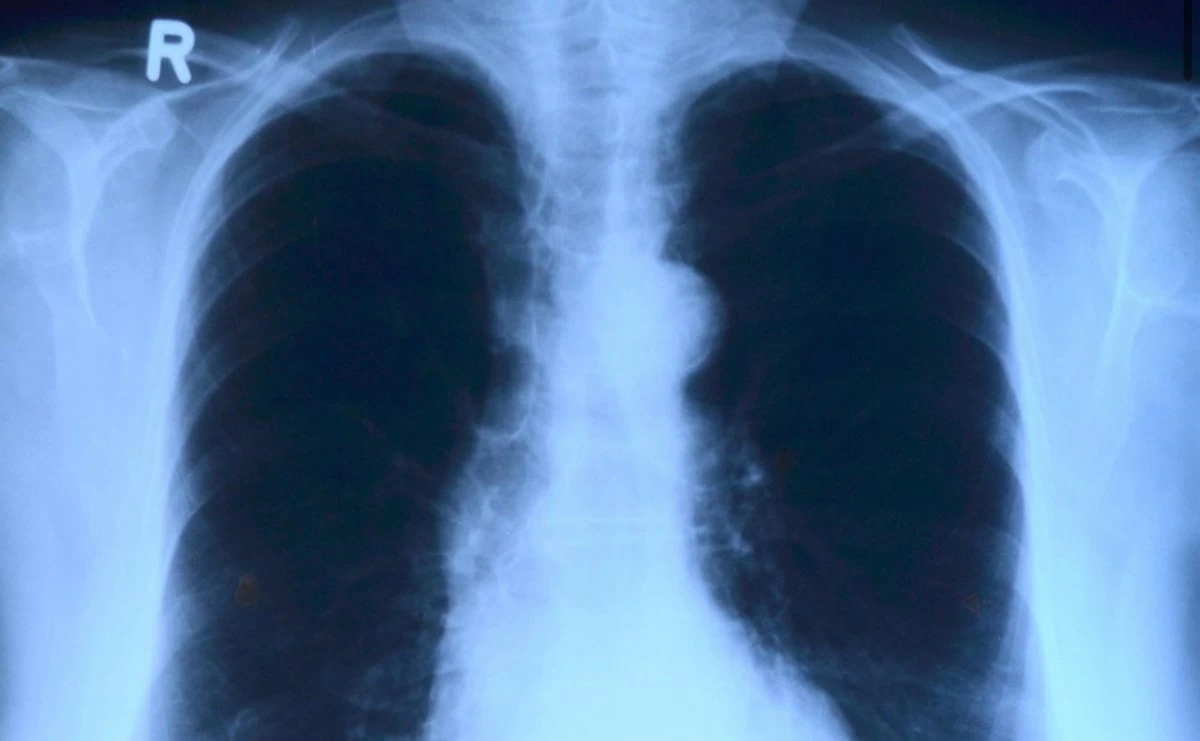

(PHOTO: PIXABAY)